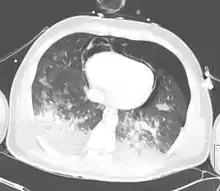

| A CT scan showing a pulmonary contusion (red arrow) accompanied by a rib fracture (purple arrow) | |

Computed tomography

Computed tomography (CT scanning) is a more sensitive test for pulmonary contusion,[6][33] and it can identify abdominal, chest, or other injuries that accompany the contusion.[38] In one study, chest X-ray detected pulmonary contusions in 16.3% of people with serious blunt trauma, while CT detected them in 31.2% of the same people.[45] Unlike X-ray, CT scanning can detect the contusion almost immediately after the injury.[43] However, in both X-ray and CT a contusion may become more visible over the first 24–48 hours after trauma as bleeding and edema into lung tissues progress.[46] CT scanning also helps determine the size of a contusion, which is useful in determining whether a patient needs mechanical ventilation; a larger volume of contused lung on CT scan is associated with an increased likelihood that ventilation will be needed.[43] CT scans also help differentiate between contusion and pulmonary hematoma, which may be difficult to tell apart otherwise.[47] However, pulmonary contusions that are visible on CT but not chest X-ray are usually not severe enough to affect outcome or treatment.[37]